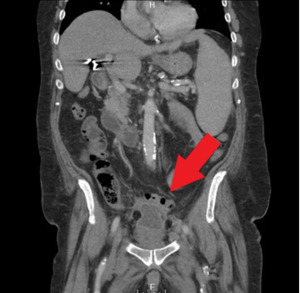

Orthopedics was the first service to evaluate the patient on hospital Day 2 and ordered a CT of the abdomen and pelvis with contrast. This study found that superior to the bladder, there was a 4.9 x 3.8 cm fluid collection with peripheral enhancement concerning for abscess. (Image 2) Internal Medicine then evaluated the patient and reviewed the results of the CT scan. Blood cultures were obtained and the General Surgery service was consulted. A repeat CT with oral contrast was ordered by General Surgery on hospital Day 3. This test showed that the adjacent loops of the intestines along the anterior and superior margin of the fluid collection were partially opacified without obvious extravasation of oral contrast in the region, suggesting fistula (i.e., communication with the bowel). (Image 3)